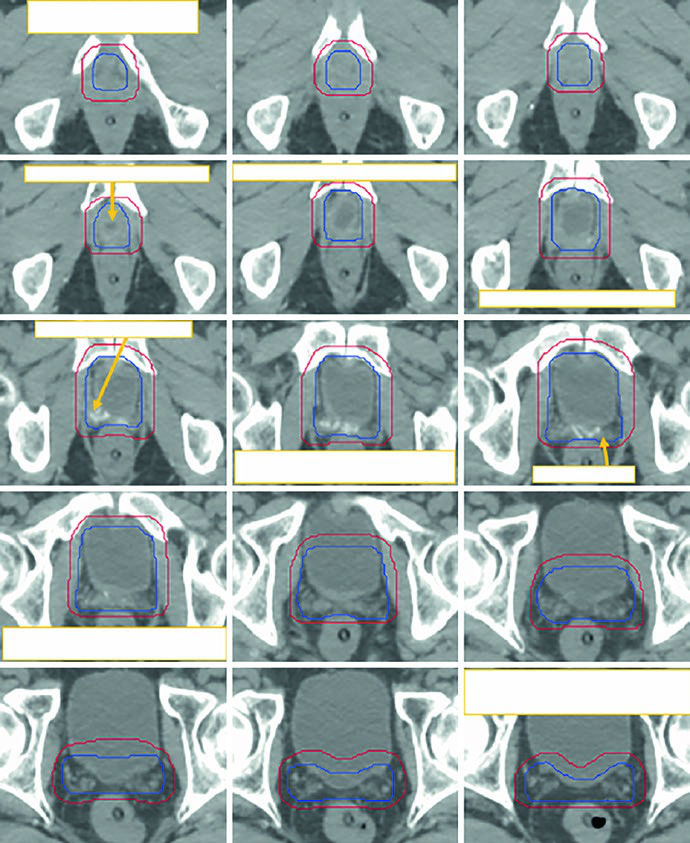

A Fig. 25.3 mostra esse raciocínio com clareza. As imagens seguem da porção caudal para a cranial em uma TC de 2 mm com protocolo de bexiga cheia. A legenda exibe o CTV inicial em azul e a modificação manual do PTV em vermelho, exatamente para evitar excesso de dose no reto quando a expansão gera cranialmente aquela configuração em halter na região anterolateral retal. Não é só uma figura bonita. É um exemplo de como a expansão automática precisa ser revisada quando a anatomia operada cria espaços novos e contornos contraintuitivos.

A Fig. 25.4 aprofunda esse ponto ao projetar o PTV em vistas ortogonais. Diferentemente do plano para próstata intacta, o pós-operatório inevitavelmente aproxima o volume da bexiga e do reto para cobrir possíveis focos microscópicos, incluindo o espaço perirretal anterior, a anastomose vesicouretral e os novos planos criados entre bexiga posterior, assoalho pélvico e VUA. A legenda destaca a sobreposição do PTV com reto em verde e bexiga em amarelo. A inspeção 3D garante que o limite anterior do PTV afile de forma progressiva acima da sínfise púbica. Quando essa transição fica abrupta, as mudanças diárias de enchimento vesical tornam o targeting mais suscetível a erro.